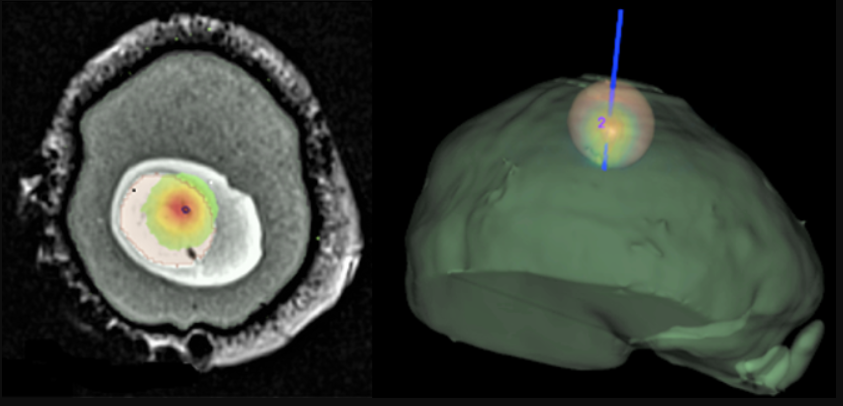

ALPhANOV développe des sources et procédés laser exploitant une multitude de mécanismes d’interaction avec les biomatériaux et les tissus vivants comme la photo-thermie, la photoablation, la photo-activation ou encore la bio-impression. Ces techniques permettent, grâce à la haute directivité et précision spatiale et temporelle des lasers, de développer des thérapies précises et mini invasives réduisant ainsi les douleurs, les complications post-opératoires et améliorant les effets hémostatiques.

ALPhANOV offre ainsi une infrastructure technologique et une expertise unique pour accompagner les industriels, chercheurs et cliniciens dans le développement de techniques chirurgicales et thérapeutiques innovantes à base de laser dans différents domaines cliniques comme la cardiologie, la neurologie, l’ostéotomie ou encore l’urologie.